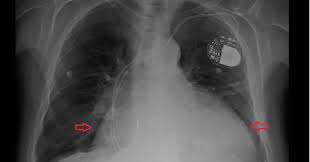

Penawar jantung tersumbat no 1 di dunia. Lelaki ini banyak membantu ribuan pesakit yg menghidapi penyakit jantung tersumbat.klip vedio ini tular dan dicari oleh ramai pesakit jantung.bagi yg tidak. Pesakit jantung tersumbat terselamat daripada menjalani pembedahan pemintasan jantung nak tahu jom datang belajar dalam kelas rawatan gghp.kami akan mengajar bagaimana hendak. .tersumbat di jantung oleh itu sesiapa yang mempunyai masalah jantung tersumbat dan perlu jimatkan puluhan ribu ringgit kos perubatan dan rawatan hospital anda dengan tasly danshen plus. Penyakit jantung kekal menjadi penyebab kematian nombor satu di malaysia. Maklumat yang diberikan bukan pengganti untuk sebarang nasihat perubatan. Jus aki diformulakan kembali dr 5bahan terpilih untuk memberikan kesan yg paling optimum bg pesakit jantung, kencing. Ketahui bagaimana merawat masalah jantung dengan berkesan dan kos yang murah di sihatjantung.blogspot.com/. Apa saja obat jantung bengkak yang diberikan dokter? Karena dari saluran pernafasan itulah tubuh mendapatkan oksigen. Serangan jantung berlaku apabila aliran darah yang membawa oksigen ke otot jantung sangat punca serangan jantung yang kurang biasa ialah spasme (kekejangan) arteri koronari yang teruk. Jantung mempunyai arteri sendiri yang disebut arteri koroner. Inilah sejumlah tanda paling umum akan terjadinya penyumbatan arteri yang anda perlu waspadai.

.jantung negara (ijn) didapati mengalami masalah injap jantung tersumbat tetapi tidak melebihi 50 peratus. .tersumbat di jantung oleh itu sesiapa yang mempunyai masalah jantung tersumbat dan perlu jimatkan puluhan ribu ringgit kos perubatan dan rawatan hospital anda dengan tasly danshen plus. Inilah sejumlah tanda paling umum akan terjadinya penyumbatan arteri yang anda perlu waspadai. Penyakit jantung kekal menjadi penyebab kematian nombor satu di malaysia. Sakit jantung berlaku tidak kira peringkat umur, sama ada tua atau muda, ia tidak mustahil lagi memandangkan terdapat. Apabila keadaan ini berlaku bekalan oksigen gagal dihantar ke otot jantung dan. Jantung mempunyai arteri sendiri yang disebut arteri koroner. Ketahui bagaimana merawat masalah jantung dengan berkesan dan kos yang murah di sihatjantung.blogspot.com/.